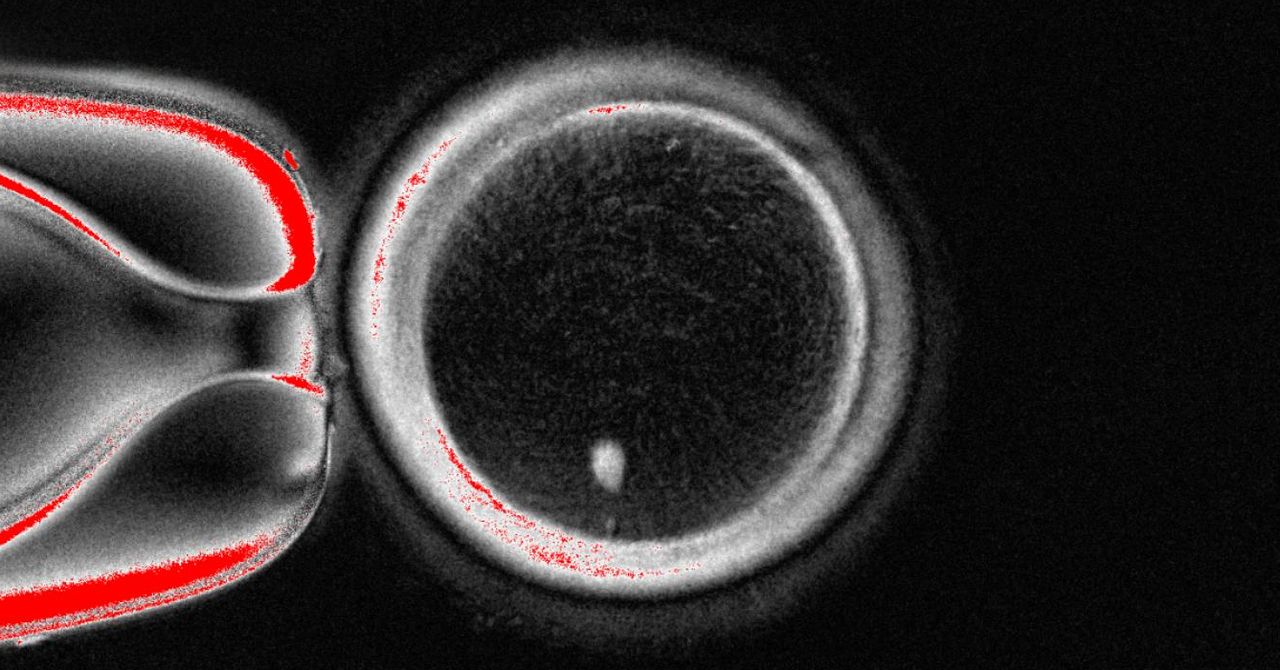

Mitinori Saitou at Kyoto University first documented in 2018 how his team turned human blood cells into stem cells, which they then transformed into human eggs, but they were too immature to be fertilized to make embryos.